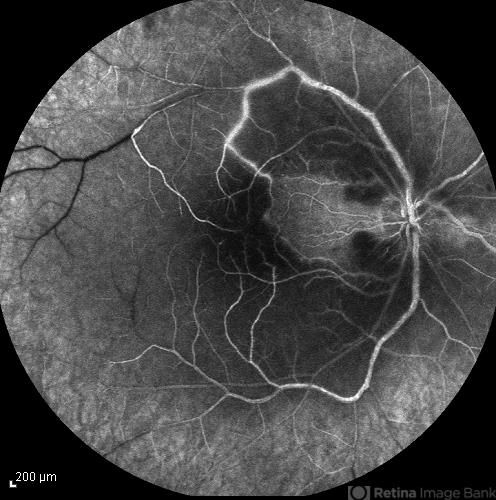

- central retinal artery occlusion (CRAO), cilioretinal sparing

- Late phase FA image of the right eye of a 34-year-old man with sudden drop of vision due to CRAO. The macula is involved despite cilioretinal artery sparing .